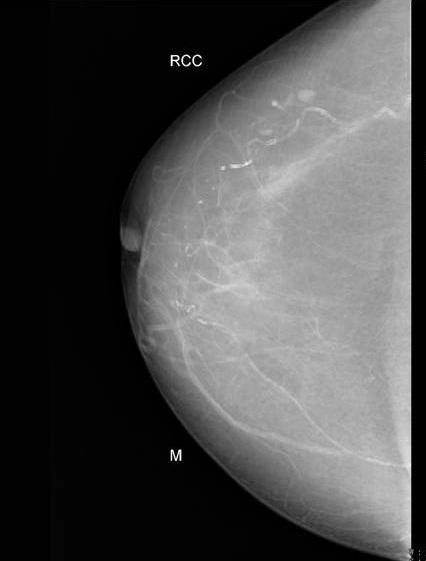

Vôi hóa tuyến vú (Breast calcifications)

Vôi hóa lành tính

Vôi hóa da ở vú (Skin calcifications in the breast)

Vôi hóa mạch máu ở vú (Vascular calcification in breast)

Vôi hóa dạng bắp rang (Popcorn-like calcification of the breast)

Vôi hóa dạng tiết dịch (secretory calcifications)

Vôi hóa dạng tròn (Round breast calcifications)

Vôi hóa nghi ngờ

Vôi hóa nghi ngờ ác tính ở vú (Suspicious breast calcifications)